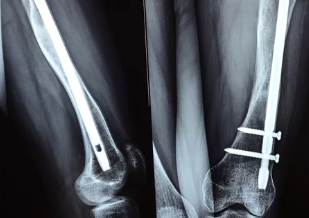

✅ (2) 경미한 충격에도 골절 위험 증가

✔ 심한 경우 낙상, 미끄러짐, 가벼운 충격에도 뼈가 골절될 가능성 증가

✔ 손목, 척추, 고관절 부위에서 골절이 잘 발생함